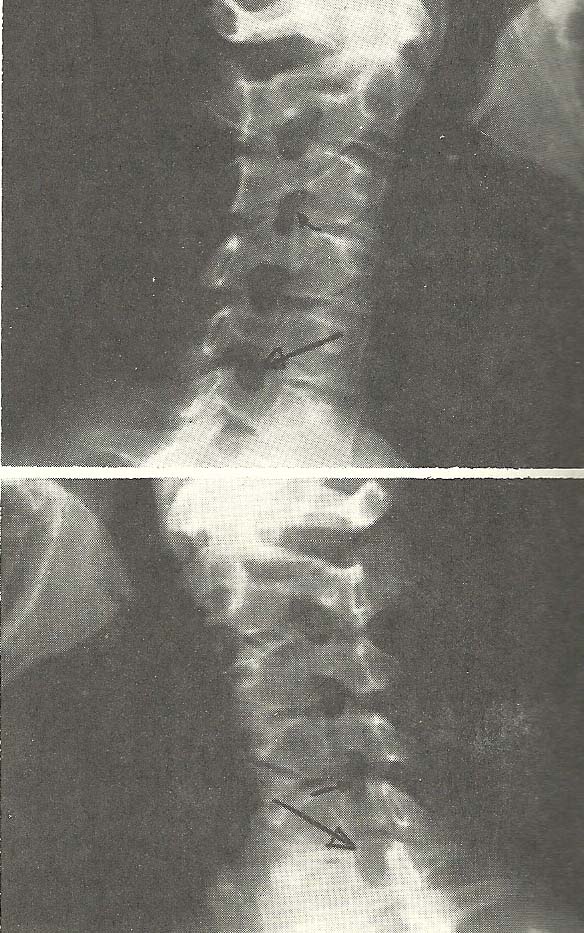

Case Illustrating Classifications B-1, C-2, C-4, A-8, and A-9

The films of this case (Figs. 6.61--6.67) show alteration of the cervical

lordosis in the neutral lateral film and lessened ability to flex the neck,

coupled with slight hypermobility during neck extension (C-4).

As the cervical curve is naturally convex toward the anterior, alteration

of this pattern usually means pathology or significant injury to the skeletal

and/or supportive structures. Note in the neutral lateral film that there is

flexion of the C3 and C4 motion units.

With neck flexion, near total fixation or hypomobility from C3 through C6

motion units (B-1) is demonstrated. The atlantoaxial and atlanto-occipital

motion units show considerably diminished ability to flex (B-1).

Extension of the neck is accomplished, even to the point of hypermobility.

All motion units extend as far as structure allows so that the posterior

arches and spinouses approximate. By comparing the three lateral films (Figs.

6.63--6.65), we have an excellent example of abnormal mobility of a spinal

section or region (C-5). Intervertebral hypomobility is present at several

levels.

This case also exhibits manifestations of other radiologically evident

subluxations. The decreased disc height at C4-C5, C5-C6, and C6-C7, due to the

evident discopathy and spondylosis, is classified as decreased interosseous

spacing (A-8). The rather marked intrusion and compromise of the neural

foramina at C4-C5, C5-C6, and C6-C7, seen on the left anterior oblique film

(Fig. 6.66), and similar alteration of the foramina at the same levels

are shown on the right anterior oblique film (Fig. 6.67), also meet the

criteria of subluxation under the classification of foraminal encroachment

(A-9).